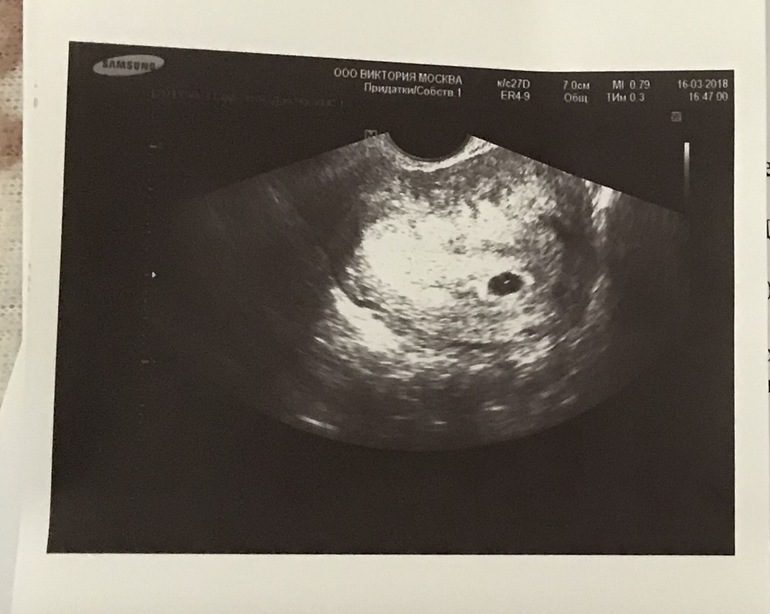

Врач собирает анамнез для уточнения наличия противопоказаний к проведению процедуры. Делает УЗИ для определения срока беременности. Берет анализы мазка на флору, группы крови и резус фактора. На первом приеме гинеколог подробно расскажет о том, как будет проходить медикаментозный аборт, какие ощущения могут быть и какие осложнения могут возникнуть. Для окончательного принятия решения, врач отпускает вас домой на 48 часов подумать.

4.Контроль УЗИ после аборта.

Для выполнения УЗИ на раннем сроке должны быть показания. Основная цель —установить маточную локализацию плодного яйца: маточная, внематочная; вторая цель — определить жизнеспособность плодного яйца. Анатомия и все остальное — уже ближе к первому скринингу в 11-14 недель, но УЗИ в ранние сроки в основном преследуют эти две цели. По определенным ультразвуковым параметрам их возможно сделать.